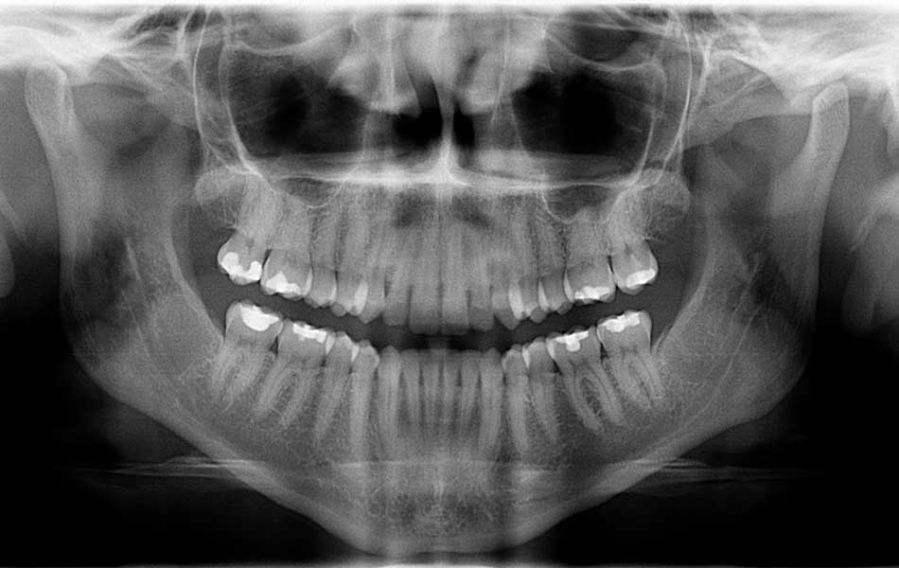

In base al numero di elementi da sostituire, le protesi mobili si suddividono in due tipi:

- protesi mobile parziale (comunemente nota come scheletrato) è usata per sostituire alcuni degli elementi mancanti nelle arcate dentali, questa tipologia di protesi utilizza gli elementi dentali rimasti per ancoraggio;

- protesi mobile totale (comunemente nota come dentiera) è usata per la sostituzione di tutti i denti del paziente, questa tipologia di protesi utilizza le mucose ed effetto ventosa per la propria posizione.